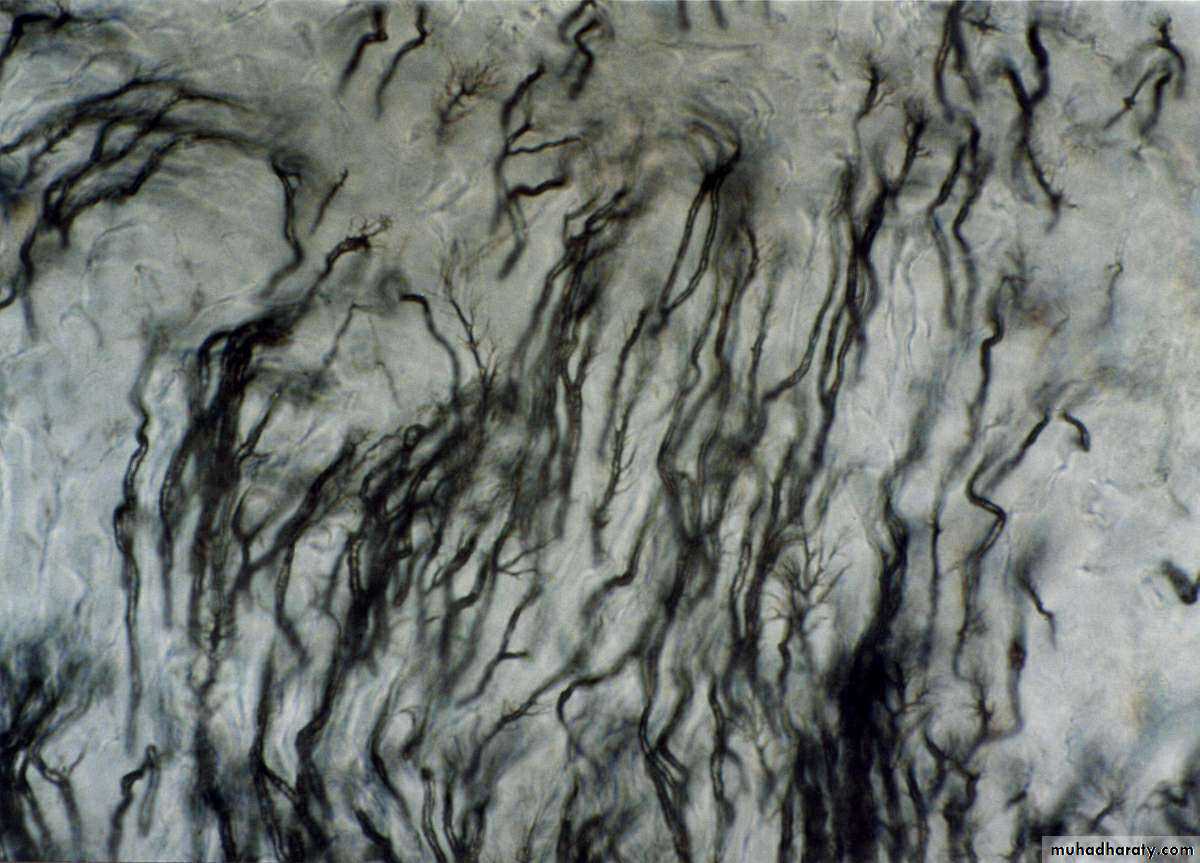

Tomes’ Granular Layer

(Size) Small granular in appearance

(Cause) it results from the looping of the terminal portions of DT which is a result different orientation of odontoblastic process (always present) .

(Site) Appear in the root adjacent to the cementum.

(IL) Does not follow any incremental pattern.